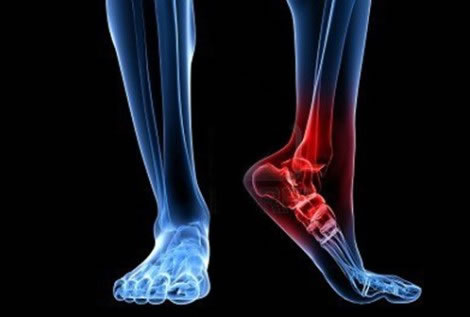

El tobillo es la articulación que conecta la pierna con el pie. En ella se relacionan tres huesos: tibia, peroné y astrágalo. Esta estructura ósea está fuertemente reforzada por músculos, tendones y potentes ligamentos que la estabilizan.